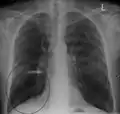

A chest X-ray is not useful to establish a diagnosis of COPD but it is of use in either excluding other conditions or including comorbidities such as pulmonary fibrosis and bronchiectasis. Characteristic signs of COPD on X-ray include hyperinflation (shown by a flattened diaphragm and an increased retrosternal air space) and lung hyperlucency.[5] A saber-sheath trachea may also be shown that is indicative of COPD.[111]

Chest X-ray demonstrating severe COPD: Note the small heart size in comparison to the lungs.